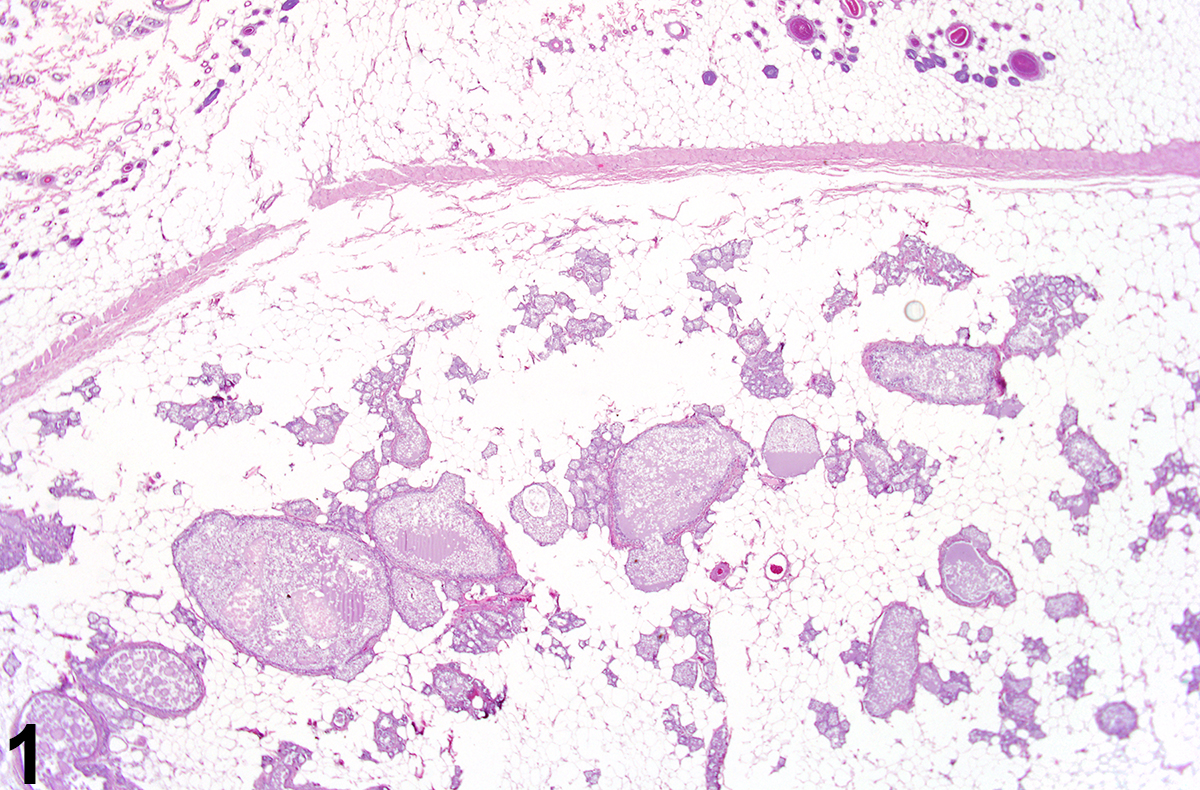

Mammary gland - Dilation in a female F344/N rat from a chronic study. There are scattered ducts and alveoli distended by intraluminal accumulations of amorphous, secretory material.

Mammary gland dilation can affect ducts, alveoli, or both. It is often a diffuse change characterized by distention of collecting (lactiferous) ducts and alveoli beneath a nipple by intraluminal accumulations of amorphous, proteinaceous eosinophilic, secretory material, lipid, cell debris, and, sometimes, inflammatory cells. The lining epithelial cells of duct dilation are often vacuolated and can occur with or without epithelial hypertrophy or hyperplasia. Galactoceles are considered an extreme form of dilation and are characterized by focally dilated mammary gland ducts and alveoli that have become cystic and very large, lined by flattened epithelium, and filled with proteinaceous secretory fluid. Galactoceles may rupture and be associated with inflammation and fibrosis.